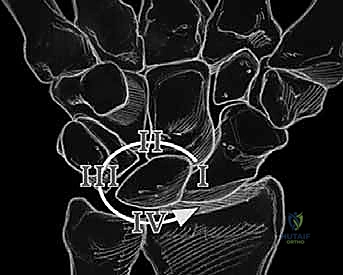

- Volar Intercalated Segment Instability (VISI): This is a more severe form of carpal collapse. While LT dissociation is a prerequisite, VISI requires additional compromise of secondary restraints, most notably the dorsal radiotriquetral ligament. Without the integrity of this extrinsic ligament, static carpal instability ensues, characterized by a volar-flexed lunate and an abnormal lunotriquetral angle. On a lateral radiograph, a normal lunotriquetral angle is approximately 14 degrees. In VISI, this angle can increase to -16 degrees or more, indicating volar flexion of the lunate.

FIG 1 • A. Intact dorsal ligaments and normal carpal alignment. Loss of integrity of these secondary restraint structures, the volar-flexed position of the lunate, and the resulting volar intercalated segment instability (VISI) carpal collapse. B. Normal anatomic alignment of the carpus as viewed from a lateral radiograph. The lunotriquetral angle is 14 degrees. C. VISI carpal collapse visible on lateral radiograph. The lunate is volar-flexed and the lunotriquetral angle is 16 degrees. D. Rupture of the lunotriquetral interosseous ligament and the dorsal secondary restraint.